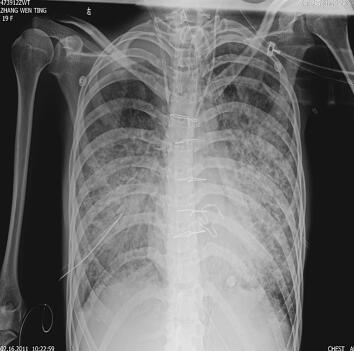

第二阶段(入院后第7~26天):二尖瓣置换术后患者心功能明显改善,多次复查心脏超声均提示心脏舒张及收缩功能未见明显异常,瓣膜功能良好。但患者感染难以控制,考虑感染源:①肺部感染:无法脱离ECMO,胸片提示双肺渗出影(图1),多次痰培养结果均提示鲍曼不动杆菌(MDR);②血源性感染:多次外周血及导管血培养提示洋葱伯克霍尔德菌;③感染性心内膜炎:考虑患者存在急性感染性心内膜炎,瓣膜赘生物形成,多为革兰阳性杆菌感染,但赘生物培养却未见细菌生长。鉴于以上感染相关证据,调整抗感染治疗方案为达托霉素和美罗培南联合左氧氟沙星,并加强气道管理,入院24天后病情明显好转,感染得到控制,逐渐增加呼吸机支持条件,并降低ECMO辅助条件,患者氧合及循环情况均未见恶化,复查胸片渗出较前吸收(图2~图4),故入院后第26天脱离ECMO,在常规机械通气的情况下,患者指脉氧饱和度可维持在95%左右,监测乳酸在1.0mmol/L左右,经皮氧分压88mmHg,经皮二氧化碳分压50mmHg。

图2 入院第26天胸片